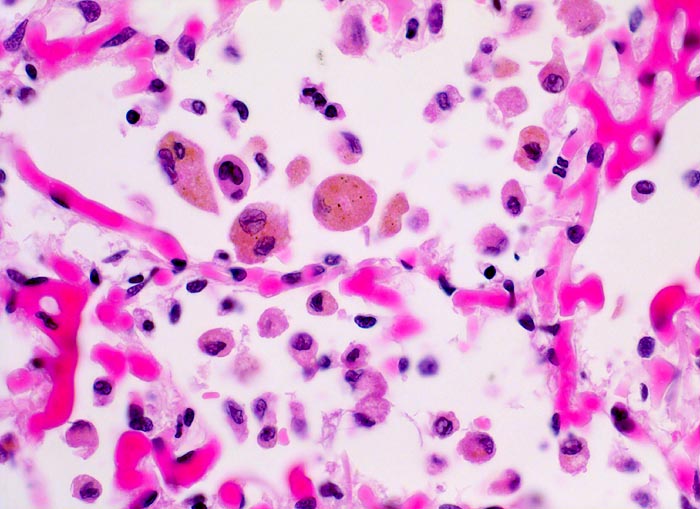

chronische Lungenstauung: Herzfehlerzellen

Die Kapillaren in den Alveolarsepten sind prall mit Blut gefüllt (Stauung). Bei sehr starker Stauung kann ein Teil des Blutes in die Alveolarräume übertreten und wird dort von den Alveolarmakrophagen phagozytiert. Deren Zytoplasma ist mit braungelbem Hämosiderin gefüllt. Daneben finden sich auch kleinere Makrophagen mit reichlich fein vakuolisiertem Zytoplasma.

Patient mit koronarer Herzkrankheit und Linksherzinsuffizienz.